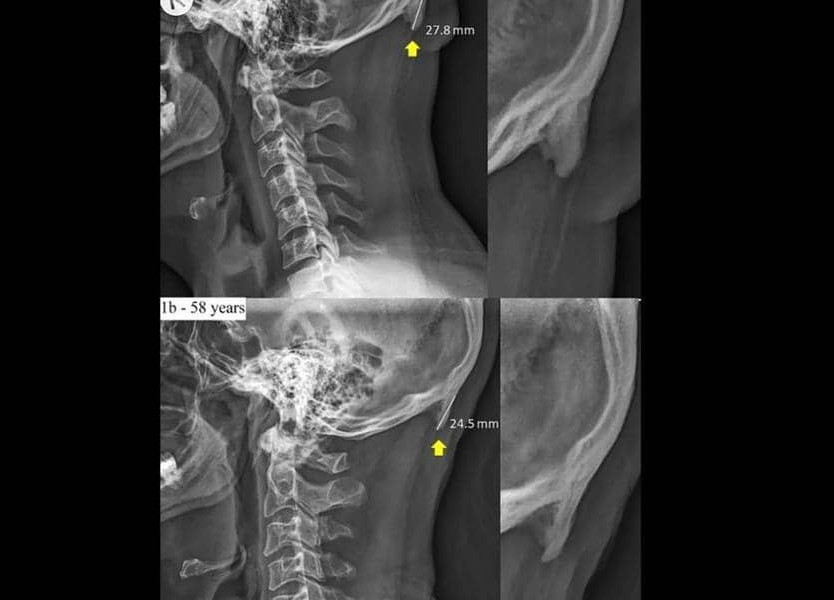

الجمهورية دراسة تحذر من شوكة الجمجمة والسبب الهواتف